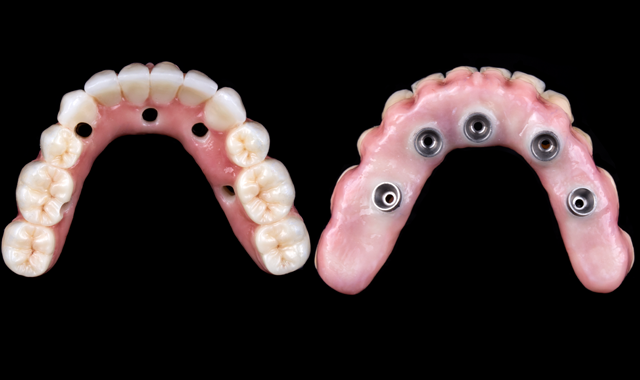

The final design of the zirconia prosthesis was done with monolithic zirconia for posterior teeth and only facial cut-back from canine to canine for porcelain veneering (Noritake CZR) and pink porcelain for the soft tissue area (GC Initial). A zirconia blank (Argen Z Esthetic 22 × 95 mm, Argen) was used for milling the definitive prosthesis (Figs. 12-13). The final zirconia restoration demonstrated excellent esthetic results (Figs. 14-15)

Fig. 12

Fig. 13